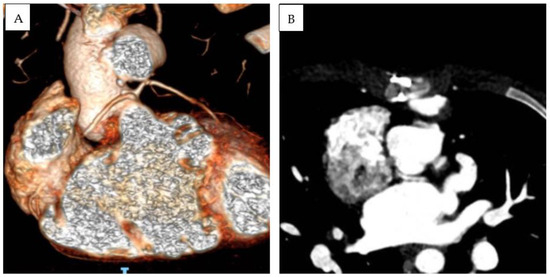

3.2. S,D,D Double-Outlet Left Ventricle with RV Hypoplasia

Patient 1 was diagnosed with (S,D,D), double-outlet left ventricle, and a hypoplastic right ventricle. An echocardiographic evaluation revealed situs solitus, D-loop, and severe hypoplasia of the right ventricle. A large, unrestrictive atrial septal defect was present. The aorta overrode a large, doubly committed, juxta-arterial VSD with an absence of infundibular septum. The great arteries were transposed and the aorta was on the right and slightly posterior to the pulmonary artery, which was completely committed to the left ventricle. A tenuous mitro-aortic discontinuity and a well-developed subpulmonary conus were present. Crossed pulmonary arteries were observed, and a subsequent CT scan showed two adjacent, side-by-side coronary ostia, located in the anterior-facing sinus, which gave origin to the left anterior descending (LAD) and the right coronary artery (RCA). The left circumflex artery (LCx) had a retroaortic course originating from the RCA (Figure 1A–C). Pulmonary banding was performed as initial palliation. At 6 months of age, the patient was scheduled for Damus–Kaye–Stansel (DKS), and bidirectional Glenn palliation and extracardiac Fontan palliation were completed at 2.9 years. Follow-up MRI showed mild pulmonary valve regurgitation and pulmonary flow discrepancy between the LPA and RPA (ratio 33% versus 67%), with normal ventricular volumes and preserved ventricular function (LV end-diastolic volume 78 mL/m2, LVEF 53%). To date (follow-up time 5.3 years), the patient is in good clinical condition and his arterial oxygen saturation is stable (SpO2 85%).

Figure 1.

Three-dimensional CT-scan (A), MRI (B), and echocardiographic (C) subcostal view showing double-outlet left ventricle, subaortic VSD, d-transposed aorta and Damus–Kaye–Stansel palliation. Absence of an infundibular septum is a common finding (arrow). LAD and RCA originate from two adjacent, side-by-side coronary ostia from the anterior-facing sinus (asterisk).